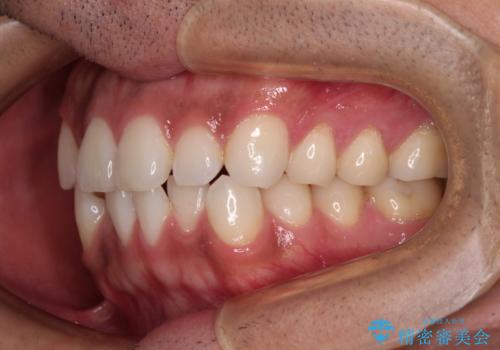

目立たない装置でデコボコを改善 ハーフリンガルによる矯正治療

- 30代男性

- 矯正装置

- ハーフリンガル

- 治療期間

- 1年4ヶ月

- 上下顎歯列のデコボコを改善したいとのことで来院された患者様です。

自己管理の大変なインビザラインや、目立つ表側のワイヤー矯正は避けたいとのことで、

上顎だけ裏側装置のハーフリンガルにて矯正しました。

一年と数か月で矯正を終えることができました。

下顎前歯部には後戻り防止のワイヤーを装着しています。